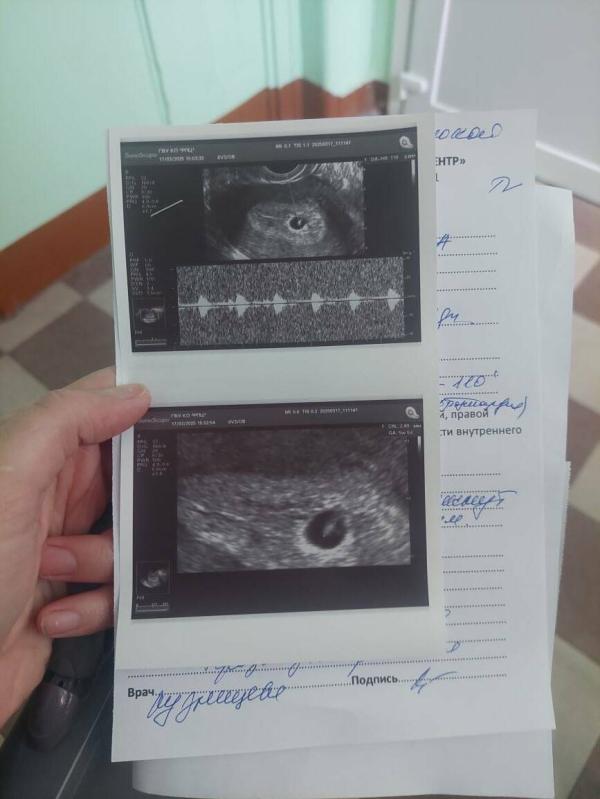

12.03 узи (плодное яйцо 8 мм, жёлтый мешочек 3мм)

Поехала сегодня в стационар по поводу замершей беремености ...Думала там ни чего уже не развивается , делают узи и говорят что ктр 3мм ,сердцебиение+ включили послушать и я в шоке.

В подвешенном состояние ,сердцебиение 143 улучлось но не растет плодное яйцо. Есть пост ,только что выложила по этому поводу